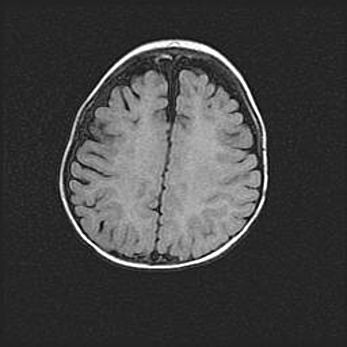

Открытая гидроцефалия.

Возраст: 6 месяцев 15 дней

Вес: 6200 г

Пол: женский

Окружность головы: 41 см

Срок гестации: 38 недель

Гидроцефалия головного мозга у новорожденных – это скопление избыточного количества цереброспинальной жидкости в головном мозге. Ее избыточное скопление в мозге приводит к патологическому расширению желудочков мозга (четырех полостей, расположенных в глубине белого вещества мозга, заполненных цереброспинальной жидкостью и связанных узкими проходами).

Открытый тип гидроцефалии (сообщающаяся) наблюдается тогда, когда нарушен механизм всасывания ликвора в системный кровоток. При этом типе причиной заболевания чаще всего является перенесенные ранее инфекции (например: менингит),  либо же наличие крови в субарахноидальном пространстве.